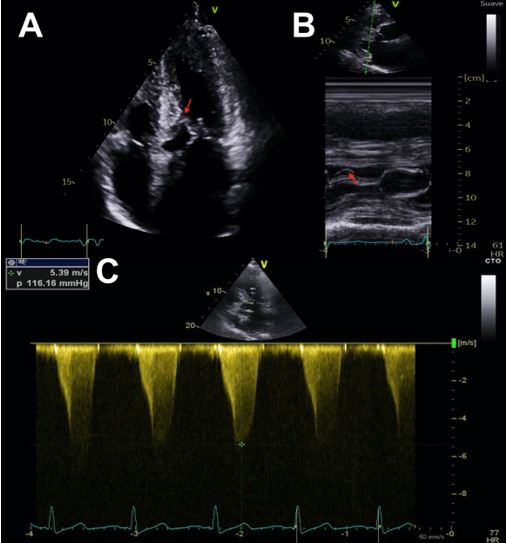

The mechanisms of MR in HCM include SAM with failure of leaflet coaptation, elongated mitral leaflets coapting in the leaflet body, anterior displacement of the mitral apparatus and PM. The anterior leaflet of the mitral valve behaves as an anterior prolapse and this arrangement in systole generates a typically mid-to-late onset eccentric lateral and posterior MR jet. Quantification of MR severity should be performed according to published recommendations and its dynamic components evaluated with provocative manoeuvres or EE3 (Figure 3).

Colour Doppler is useful to initially locate the level at which the obstruction occurs, as aliasing will occur where there is flow acceleration. To measure LV outflow tract and intraventricular gradients, continuous Doppler is used to measuring the degree of obstruction and pulsed Doppler to locate the exact point where the obstruction is occurring, since depending on the different patterns of ventricular hypertrophy, the obstruction may occur at different levels. It is therefore advisable to use pulsed Doppler from the apex to the base and outflow tract so as not to miss possible intraventricular areas of increased gradients. The typical morphological appearance of the Doppler signal is a “dagger-shaped” and late peaking curve. This is because HCM creates a vicious circle in which obstruction generates more obstruction. At the beginning of systole, ejection begins normally but as systole progresses the outflow tract narrows due to increased pressure and the pressure increases further due to the narrowing of the outflow tract thus closing the circle. Thus, the continuous Doppler contour shows a progressive flow acceleration pattern (Figure 3).